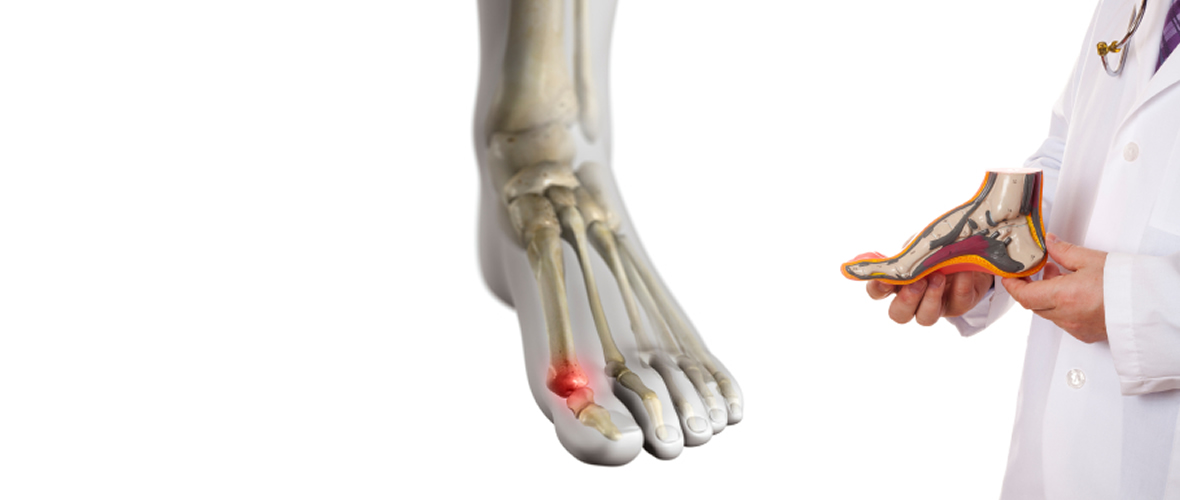

In-Office Custom Molded Foot Orthotics

A prescription foot orthosis is an in-shoe brace which is designed to correct for abnormal foot and lower extremity function (the lower extremity includes the foot, ankle, leg, knee, thigh and hip).

Podiatrists prescribe two main types of prescription foot orthoses for their patients, accommodative orthoses and functional foot orthoses. Both types of prescription foot orthoses are used to correct the foot plant of the patient so that the pain in their foot or lower extremity will improve so that normal activities can be resumed without pain.

Orthotic Laboratory

Lubbock OrthoticsCustom molded device for your shoes designed to reduce dysfunctional patterns as the foot strikes the ground.